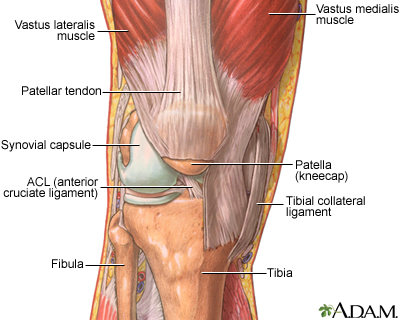

Viral arthritis is swelling and irritation (inflammation) of a joint caused by a viral infection.

The main symptoms are joint pain and swelling of one or more joints.

A physical examination shows joint inflammation. A blood test for viruses may be performed. In some cases, a small amount of fluid may be removed from the affected joint to determine the cause of the inflammation.

If joint inflammation is severe, aspiration of fluid from the affected joint may relieve pain.